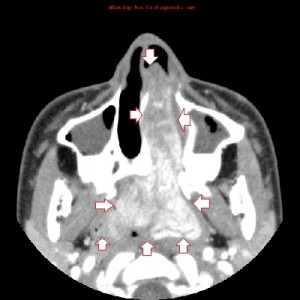

First panel, left to right: Axial contrast-enhanced maxillofacial CT scan in soft-tissue window from superior to inferior, showing a large, avidly enhancing mass in the left nasal fossa, extending posteriorly into the left nasopharnx and crossing into the right nasopharynx behind the nasal septum. Note opacification of the right and left maxillary sinuses, possibly from disturbed drainage.